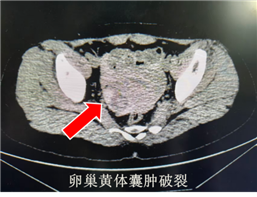

女性急腹症的诊断难点,向来在于“同症异病”的复杂局面。以CT室接诊患者为例,患者因腹痛就诊,既往具有阑尾炎病史,很容易先入为主怀疑阑尾炎复发,通过盆腔CT检查亦见阑尾增粗,管腔内见高密度粪石,然而值班医师敏锐捕捉到右侧附件区高低混杂密度这一关键特征,通过CT值测量,高度怀疑有出血,由此怀疑出发,经过仔细问询患者月经史,综合CT影像表现,最终诊断为卵巢黄体囊肿破裂。这一案例并非个例,本科室日间接诊另一病例中,同为女性腹痛来诊,CT检查可见盆腔巨大囊性肿物,经过CT室医师细致阅片后,结合解剖位置、形态特征及临床症状,诊断为卵巢囊肿蒂扭转,该患者于当日在我院手术证实该诊断正确。

影像学检查能通过清晰的图像,直观呈现腹腔内组织结构的细微变化,为疾病检备提供客观、精确的依据。CT检查在密度分辨力上占据优势,能够精准识别高低混杂密度、积液、炎性渗出等细节,尤其区分腹腔内出血、感染及实性病变时为最终确诊提供强有力的支撑,从而为临床治疗提供最可靠的决策依据,避免误诊给患者带来的不必要痛苦与治疗风险,精准破局,守护每一位患者的生命健康。